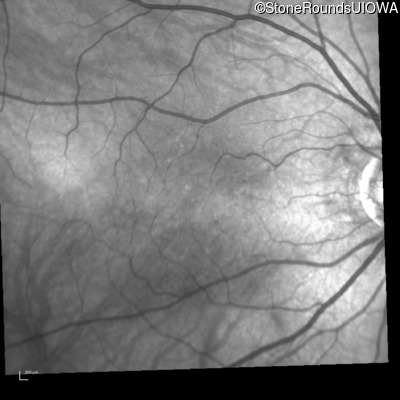

Infrared Fundus Photograph - Right - 20/200

Exemplar